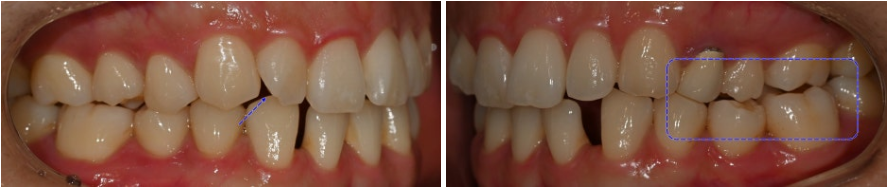

23.10.20

양쪽 교합을 확인해 보면

왼쪽 어금니 부위가

반대교합이 확인됩니다.

윗니는 삐뚤빼뚤하며

위 앞니가 아랫니를 덮는 양이 부족합니다.